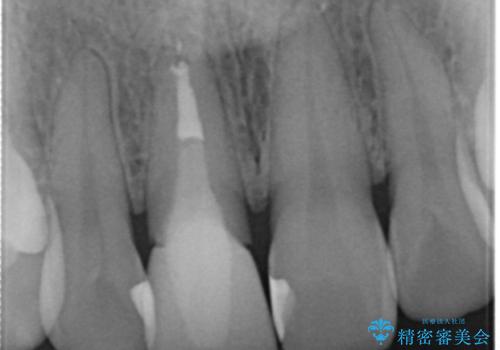

患者様の天然歯はグラデーションがあり切縁(歯冠の先端)はやや透けていて透明感があるのに対し、前歯(右上1)の差し歯はやや黄色く不透明で単調な色味でした。

患者様のご希望により、右上1はジルコニアクラウン(スペシャル)、右上5はジルコニアクラウン(スタンダード)へやりかえることにしました。

再根管治療に関しては、患者様がご希望されず症状もないため行っておりません。

ご予算の都合とご希望により、右上5の土台はやりかえずに元の土台のまま治療を進めました。